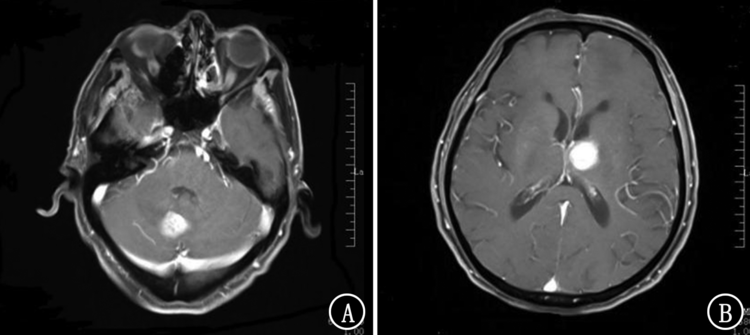

应用安罗替尼治疗小细胞肺癌伴脑转移患者一例

小细胞肺癌脑转移患者生存时间短,无有效的治疗方案。安罗替尼的适应证为三线或三线以上的非小细胞肺癌的治疗,临床上也可用于小细胞肺癌的治疗。本院应用单药安罗替尼治疗1例小细胞肺癌脑转移患者,取得了显著疗效。